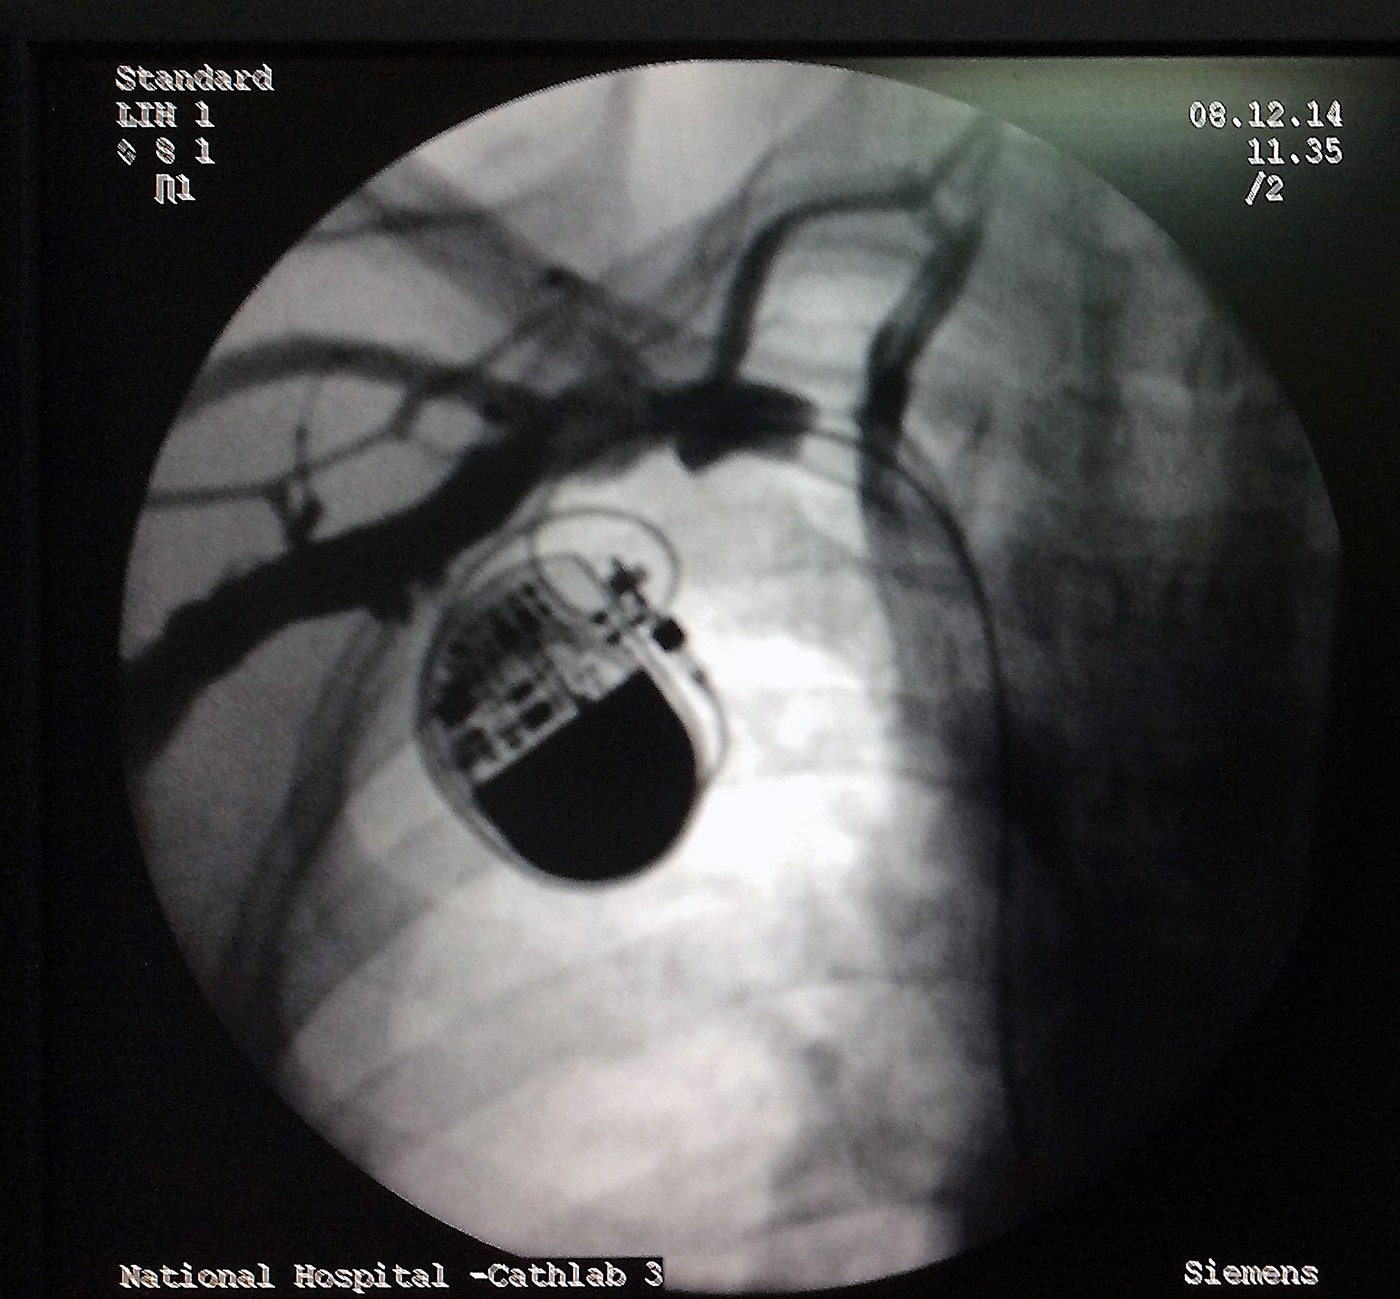

From www.howtopace.com

Role of Venography How to Pace What Is A Ct Chest Venogram This article provides a brief summary of the technique, indications, and. Learn how to perform indirect and direct ct venography and when to use this imaging modality for diagnosing venous disease. One of the advantages of ct venography over digital subtraction venography is its ability to evaluate the proximal extent of. Providers use this test to diagnose deep vein thrombosis.. What Is A Ct Chest Venogram.